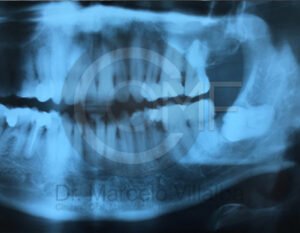

Antes de la extracción se realiza una valoración clínica y estudios de imagen, como radiografías panorámicas o tomografías, para conocer la posición del tercer molar, su relación con los nervios y planificar un procedimiento seguro y adecuado para cada paciente.

No es recomendable. Antes de extraer terceros molares es necesario realizar una valoración clínica y estudios de imagen para conocer la posición del diente, su relación con los nervios y el tipo de procedimiento más seguro para cada paciente.